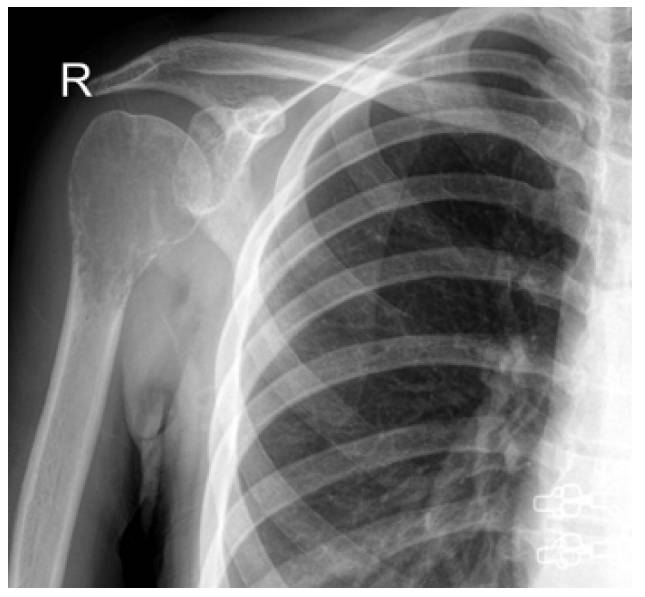

Ameliyat Öncesi: Röntgende proksimal humerus bölgesinde sınırları düzensiz litik lezyon görülmekte